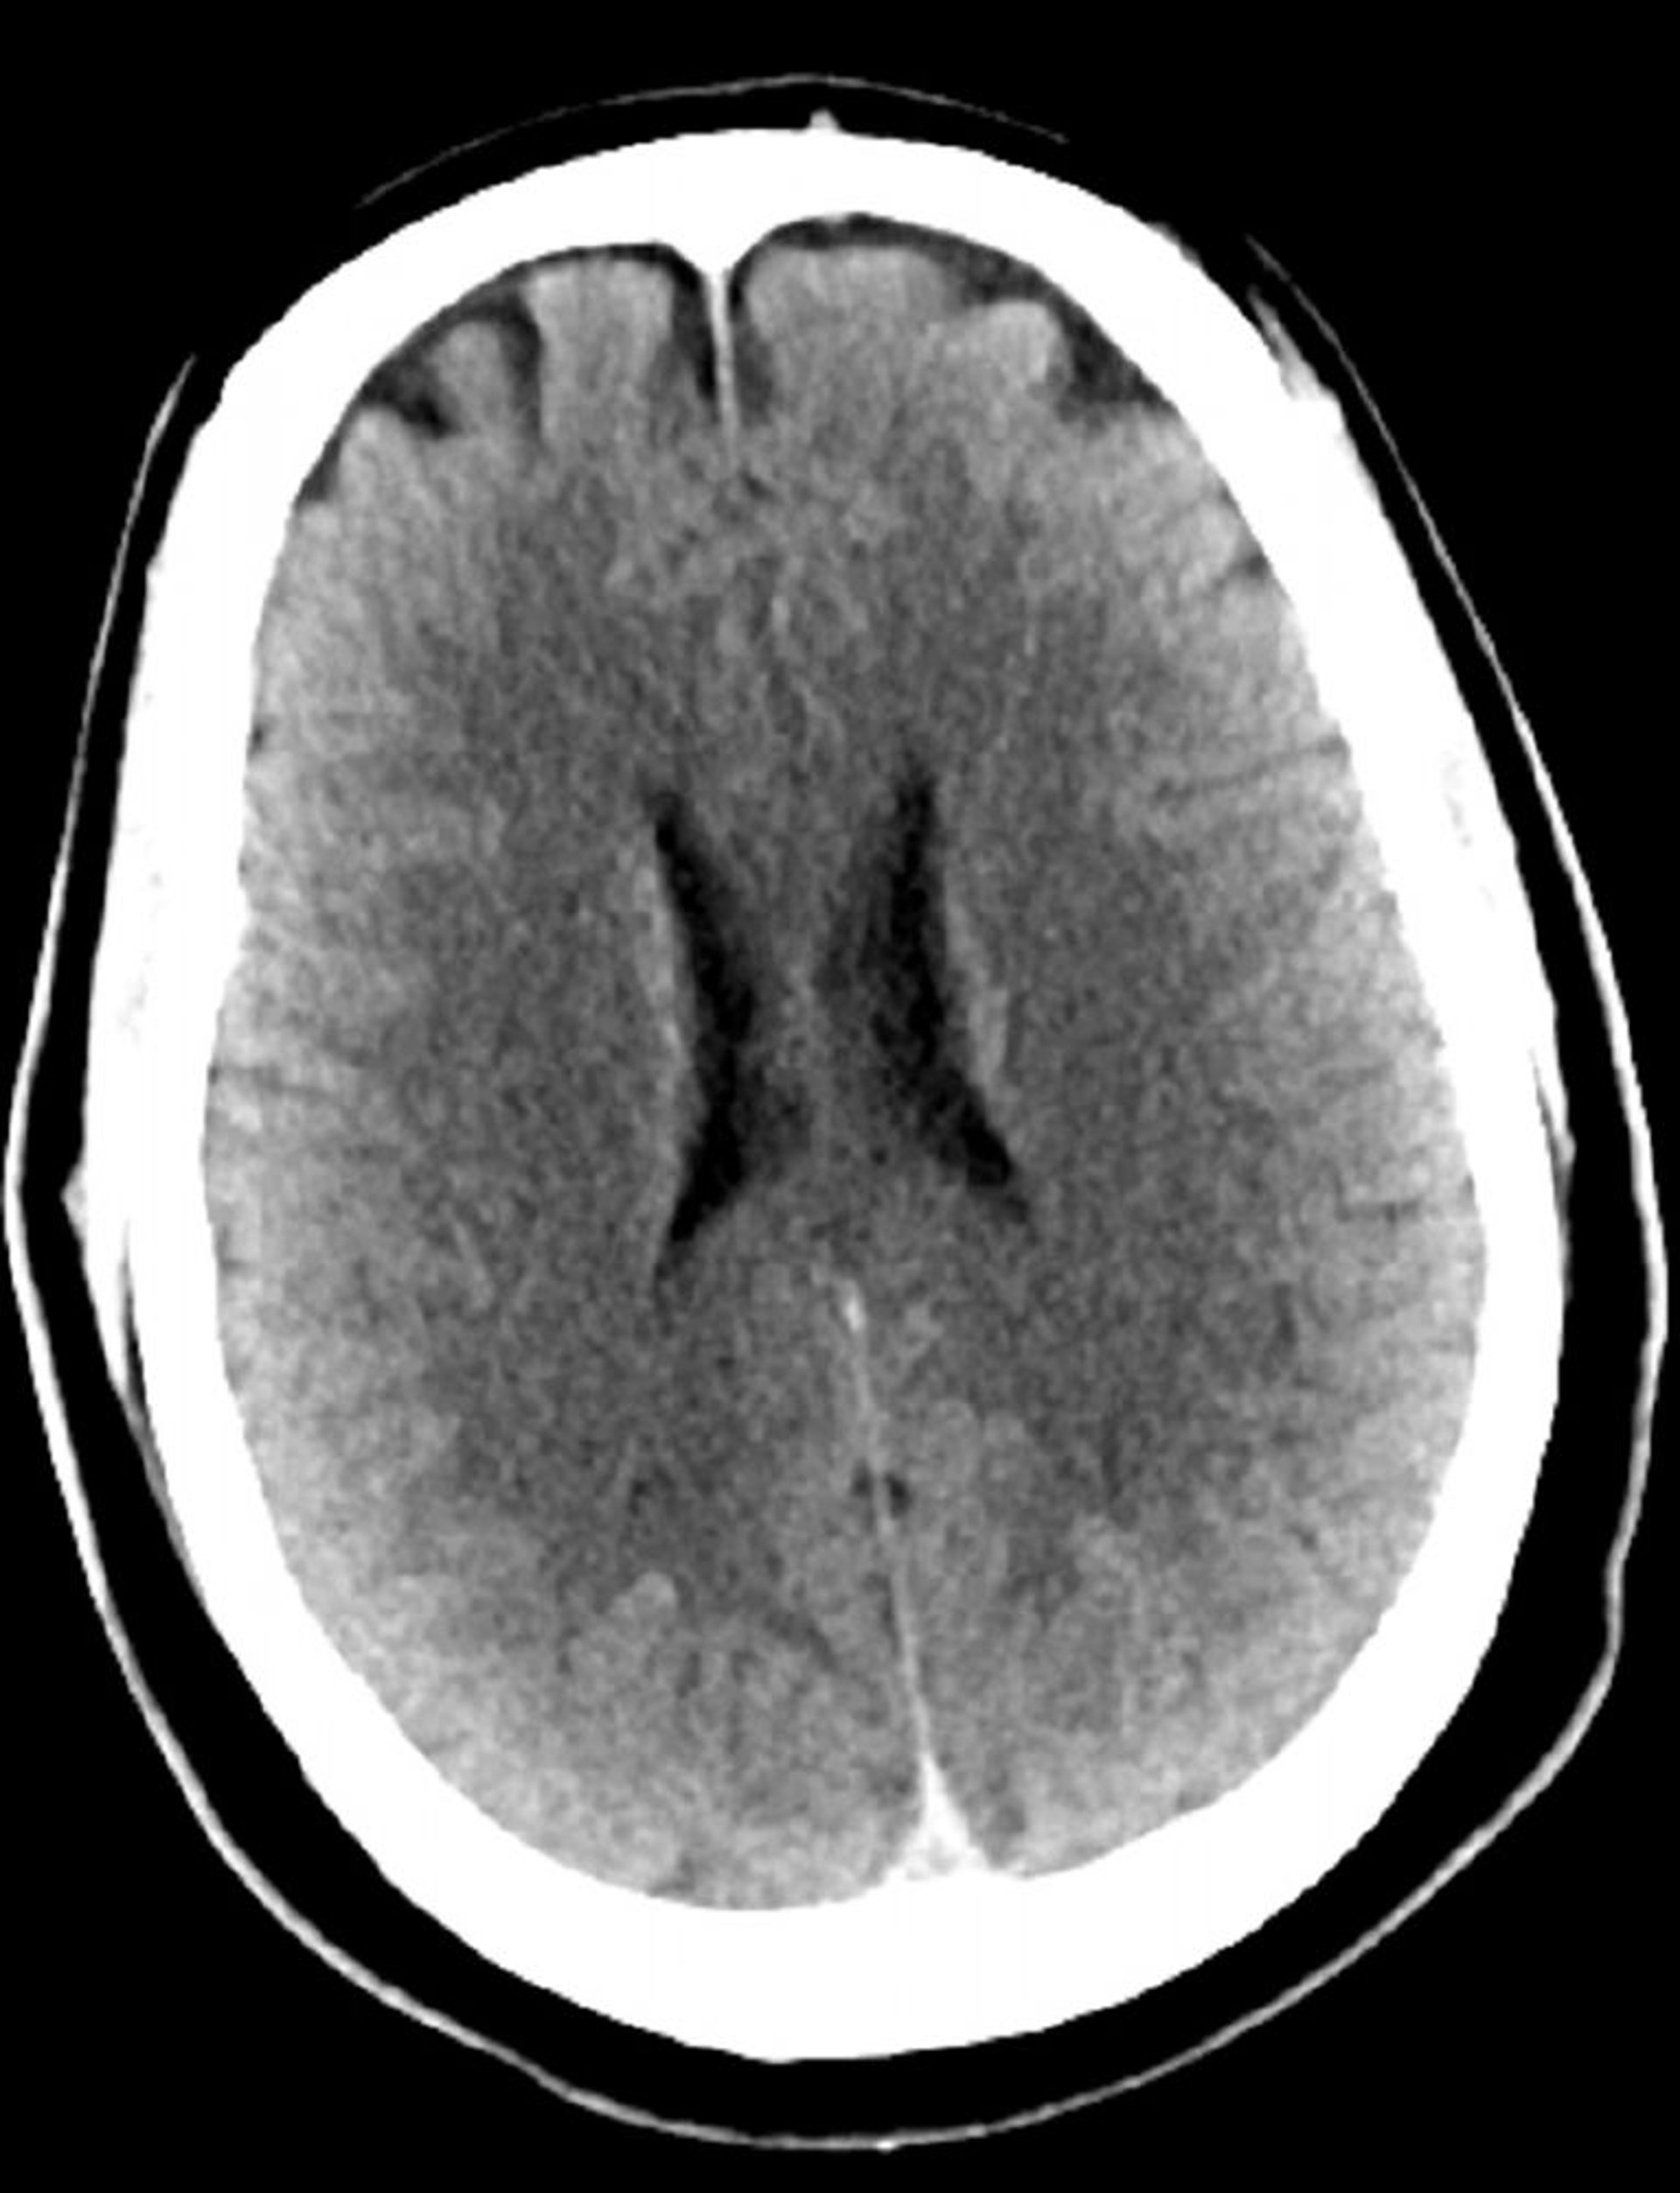

Tomografía computarizada craneal normal (adulto, 30 años)–diapositiva 3

Esta imagen es una tomografía computarizada craneal normal correspondiente a un adulto joven de 30 años de edad. No hay hemorragia o líquido intra- o extra axial. Se conserva la diferenciación gris-blanco. El tamaño ventricular y el patrón sulcal son normales.